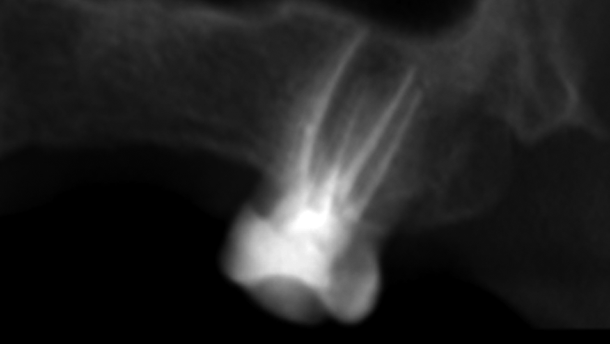

The diagnostic periapical radiograph (bisecting angle technique) showed

- partly obturated palatal and mesiobuccal (MB) root canals and an unfilled distobuccal (DB) root canal;

- slight radiolucency around the palatal root apex; no distinctive border towards the surrounding maxillary bone structure.

Two intra-oral radiographs were captured from two different horizontal angles with an inserted K-file in each root canal, but only one revealed all four root canals (Fig. 2), showing vague contours of the apical portion of the roots.